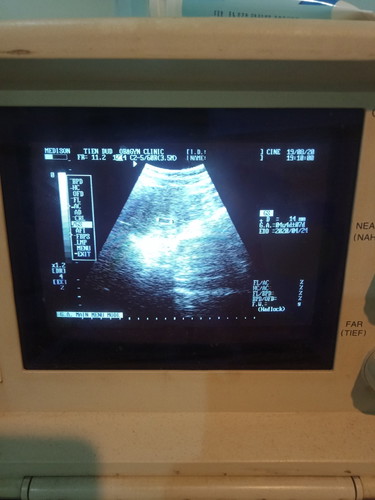

ครรภ์ 5 สัปดาห์ รูปอัลตราซาวผิดปกติมั้ยค่ะ

ตอนเเรกประจำเดือนขาด2เดือนเข้าเดือนที่3ค่ะ เเต่พอซาวน์หมอบอกว่าครรภ์ได้เเค่5สัปดาห์เอง เเถมมีอาการปวดท้องน้อยเป็นระยะๆ เเบบนั้นอันตรายมั้ยค่ะ ปกติอัลต้าซาวน์ 5 สัปดาห์รุปจะประมานนี้มั้ยค่ะ